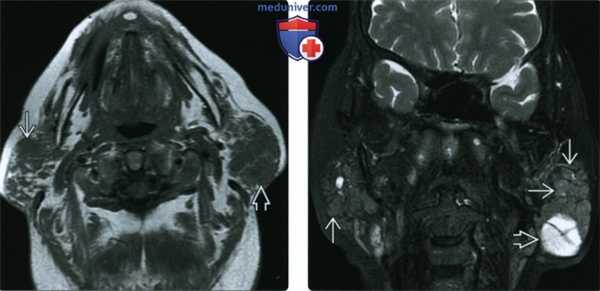

(Слева) МРТ Т1ВИ, аксиальная проекция. Увеличенные околоушные железы с неоднородной структурой. У пациента, которому 10 лет назад был выставлен диагноз синдрома Шегрена, появилось пальпируемое образование в левой околоушной области. Лечащий врач обнаружил образование и с правой стороны.

(Справа) МРТ Т2ВИ FS, коронарная проекция. В обеих околоушных железах обнаруживаются множественные образования с сигналом промежуточной интенсивности, слева также имеются солидные и кистозные структуры. После проведения аспирационной биопсии был выставлен диагноз MALT-лимфомы с обеих сторон. Пациенту был проведен курс лучевой терапии.

(Слева) На аксиальной МРТ (Т1 ВИ) определяется выраженное увеличение околоушных желез, имеющих неоднородную структуру. У пациента 10 лет страдающего болезнью Шегрена, обнаружена пальпируемая опухоль левой околоушной железы, справа в железе обнаруживается узел, определяющийся также клинически.

(Справа) На корональной MPT (Т2 ВИ FS) у этого же пациента с обеих сторон определяются множественные очаги промежуточным сигналом, а также кистозно-солидная опухоль слева вв При исследовании аспирата из очагов с обеих сторон подтвердилась MALT-лимфома. Была назначена лучевая терапия.